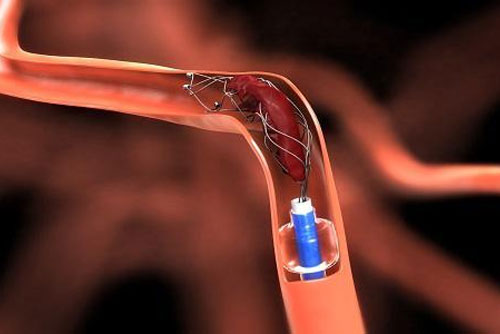

Mechanical Thrombectomy Stroke